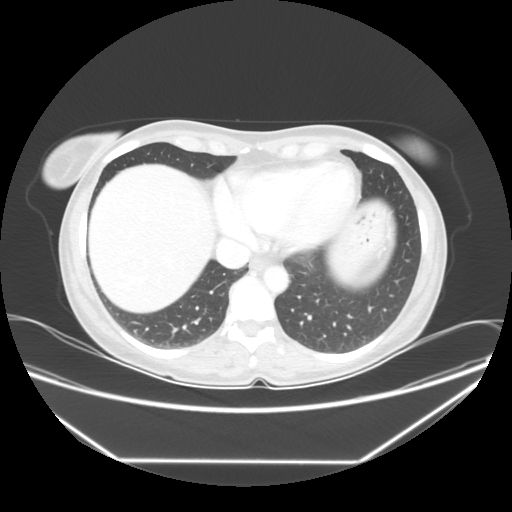

Generated VENOUS CT scan (A→B translation)

No window - Raw intensity values

Lung window (WL -600, WW 1500 β†’ Low βˆ’1350, High +150)

Mediastinum window (WL 40, WW 400 β†’ Low βˆ’160, High +240)